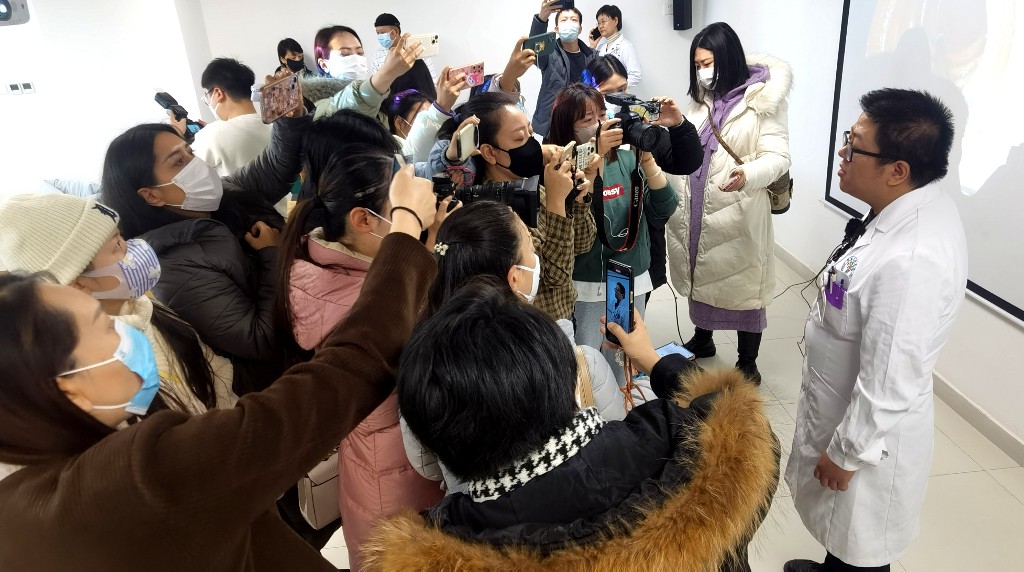

纯熟的医护团队、前沿的技术设备、完备的绿色通道机制,西安市红会医院消化内科的小肠镜检查治疗水平处于西北地区前列。

19日在消化道出血绿色通道开启后,红会医院及时联动麻醉科为患者进行麻醉评估,消化内科医护人员则迅速赶往医院进行治疗,为患者争取最佳治疗时间。同时,在手术进行中,如果出现小肠穿孔情况,消化内科配备相应的内镜下止血条件,避免患者剖腹手术的风险。消化内科的医疗团队接触小肠镜案例多、技术纯熟,可以为患者提供专业的医疗服务。